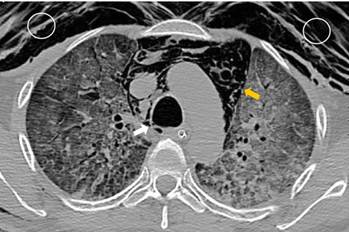

Paciente masculino de 44 años, referido de otra institución hospitalaria por deterioro de su condición respiratoria secundaria a COVID-19. Fue tratado inicialmente con ventilación mecánica no invasiva, pero desarrolló insuficiencia respiratoria severa por lo que requirió intubación orotraqueal de urgencia y ventilación mecánica invasiva. Al cabo de unas horas presentó un gran enfisema subcutáneo y neumomediastino confirmado mediante radiografía de tórax (Figura 1) y mediante tomografía computarizada de tórax, que informó además neumonía por COVID-19 severa, enfisema subcutáneo y neumomediastino masivo. Se identificó también una pequeña perforación traqueal distal de 5 mm localizada a la derecha de la parte membranosa (Figura 2). Presentó inestabilidad hemodinámica que requirió el inicio de vasopresores.